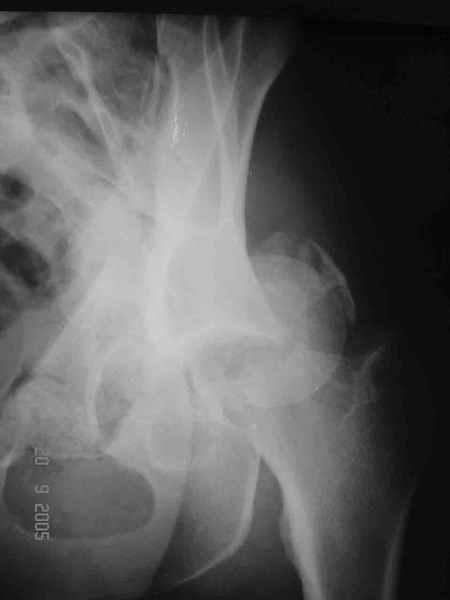

Привет! Вот недавно прооперировали похожий на ваш случай - впадина + шейка (правда у нас впадина поперечный+задний край). После травмы прошло 4 недели. мужчине 46 лет. С такой комбинацией все показания к первичному протезированию. Морально и технически мы к этому уже созрели.Но больной не собрал денег на протез. Выполнили остеосинтез впадины и шейки, прекрасно понимая, что головка вскоре рассосется, мы хотя бы надемся что к этому времени таз срастется, как говорится создали все условия для дальнейшего протезирования (может, и протез в последующем подешевле будет, в смысле, без укрепляющего кольца?). Привет Рункову!

Согласен, можно было и подлиннее. Доступ такой же - чрезвертельный, только разрез кожи прямой (а не Y, чего то я разницы не ощущаю). Головка была абсолютно свободной (то есть во время остеосинтеза таза лежала в стакане и не мешалась). Шансов, что она прирастет 0,00001%. Хотели даже выбросить, но привинтили как временный биологический протез (читай свободный трансплантат), чтоб на период срастания таза бедро проксимально не ушло (может ортопеды потом спасибо скажут). Ну а у вас первичное протезирование при переломе впадины тоже пока полько в планах?